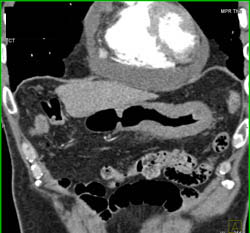

Linitis Plastica